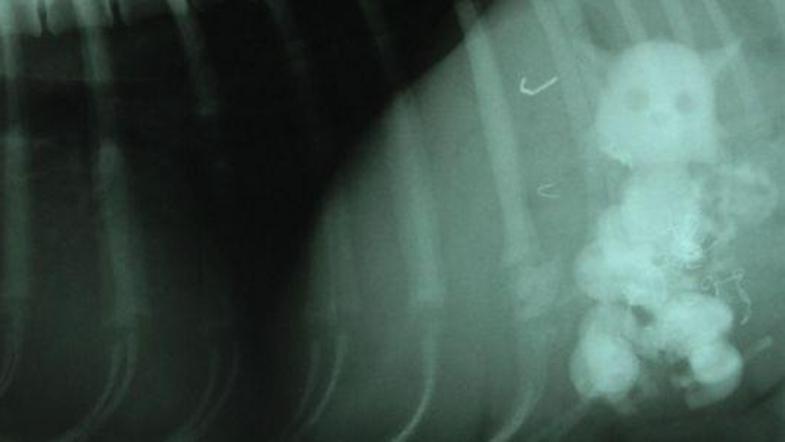

Obraz osamljene mačke na rentgenski sliki (Foto: Metro) Žurnal24 main

Enoletna Snowy, ki tehta le 3,6 kilograma, ima rada okraske. Celo tako zelo, da katerega kar poje. Veterinar je bil nad rentgensko sliko njenega trebuha naravnost presenečen. V njem so namreč našli pet igračk v podobi mačke.

"Vsi smo bili šokirani. Že deset let sem veterinar, pa česa takšnega še nisem videl. Psi ponavadi pogoltnejo žogice za golf ali baterije, a Snowy premaga vse," je povedal Nigel Belgrove.

Stanje se še vedno ni izboljšalo. Šele rentgen je pokazal pravo sliko. V enourni operaciji so ji tujke iz želodca odstranili. Psička Snowy že okreva, imela pa je srečo, da ni utrpela trajnih poškodb.